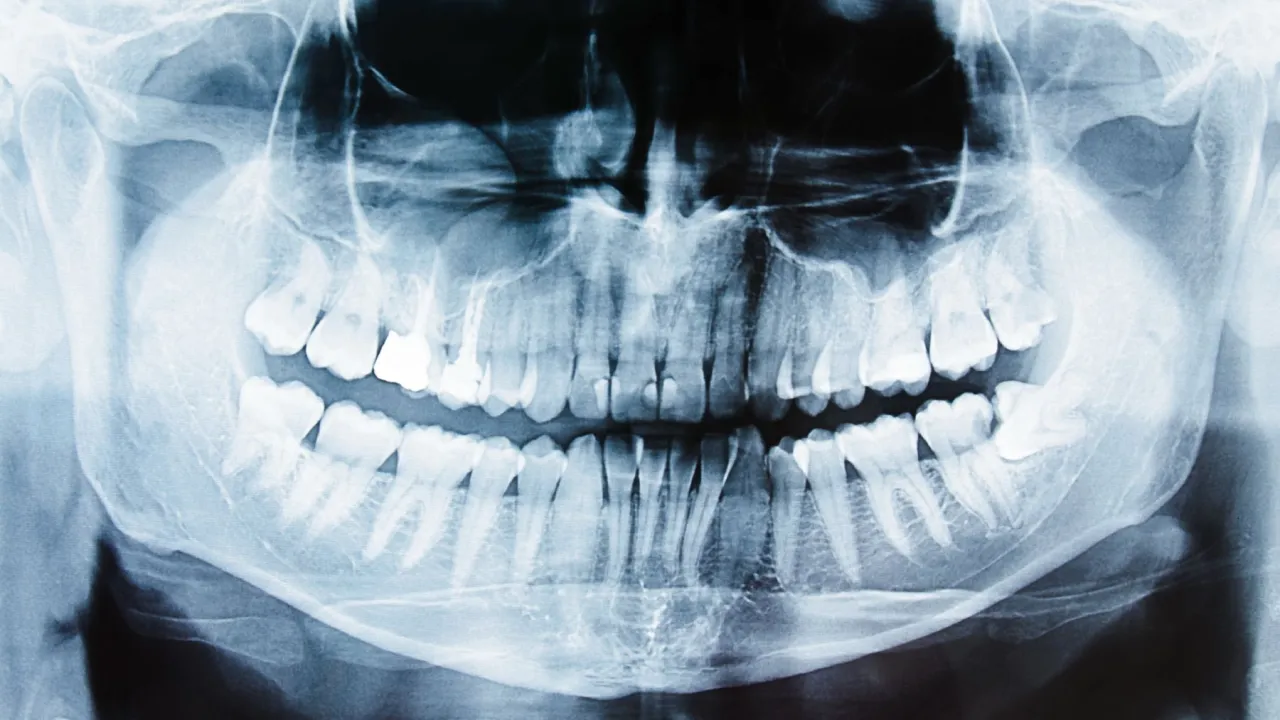

Diagnostyka to podstawa co pokaże zdjęcie RTG i dlaczego jest niezbędne

Kiedy pacjent zgłasza się do mnie z podejrzeniem pozostawionego korzenia, pierwszym krokiem jest zawsze dokładne badanie stomatologiczne. Jednak kluczowym elementem diagnostyki jest wykonanie zdjęcia RTG. Bez niego nie jestem w stanie precyzyjnie ocenić sytuacji. Zdjęcie rentgenowskie pozwala mi nie tylko potwierdzić obecność korzenia, ale co najważniejsze, dokładnie zobrazować jego położenie, kształt, długość oraz stan otaczającej go kości. Dzięki temu mogę ocenić, czy wokół korzenia rozwija się stan zapalny, czy doszło do zaniku kości, a także zaplanować najbezpieczniejszą i najskuteczniejszą metodę leczenia. To podstawa, bez której żadna dalsza decyzja terapeutyczna nie byłaby w pełni odpowiedzialna.